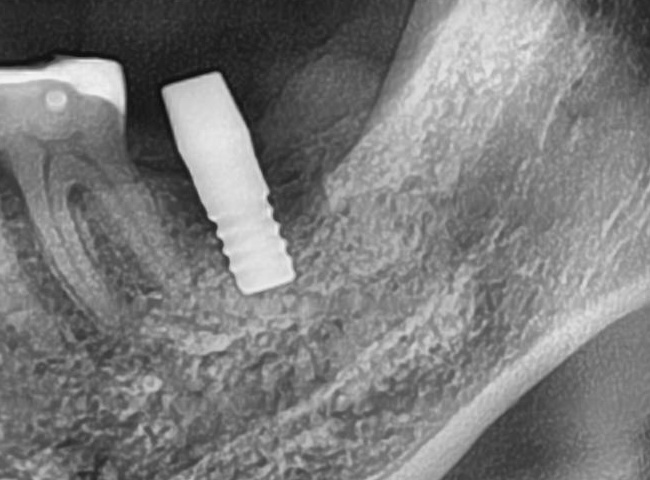

開けた穴に、専用道具を使ってネジを締めるように長さ2センチ程のインプラントを骨に埋め込んでいきます。

しっかりとインプラント埋め込まれた後は、動揺がないか、噛んだ時に当たらないかなどを確認して、最後にパノラマ写真を撮影して今回のオペは終了となりました。